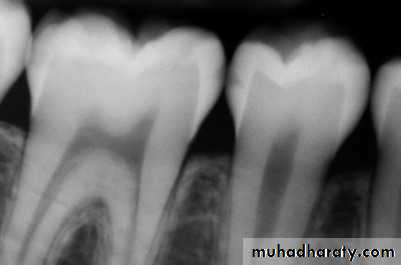

Radiographically, there may be varying degrees of pulpal calcification but no evidence of resorption, caries, or mechanical pulp exposure. No endodontic treatment is indicated for these teeth.

Typically, there are minimal or no changes in the radiographic appearance of the periradicular bone.With advanced irreversible pulpitis, a thickening of the periodontal ligament may become apparent on the radiograph, and there may be some evidence of pulpal irritation by virtue of extensive pulp chamber or root canal space calcification or even internal resorption

Radiographic changes may occur, ranging from a thickening of the periodontal ligament space to the appear-

ance of a periapical radiolucent lesion